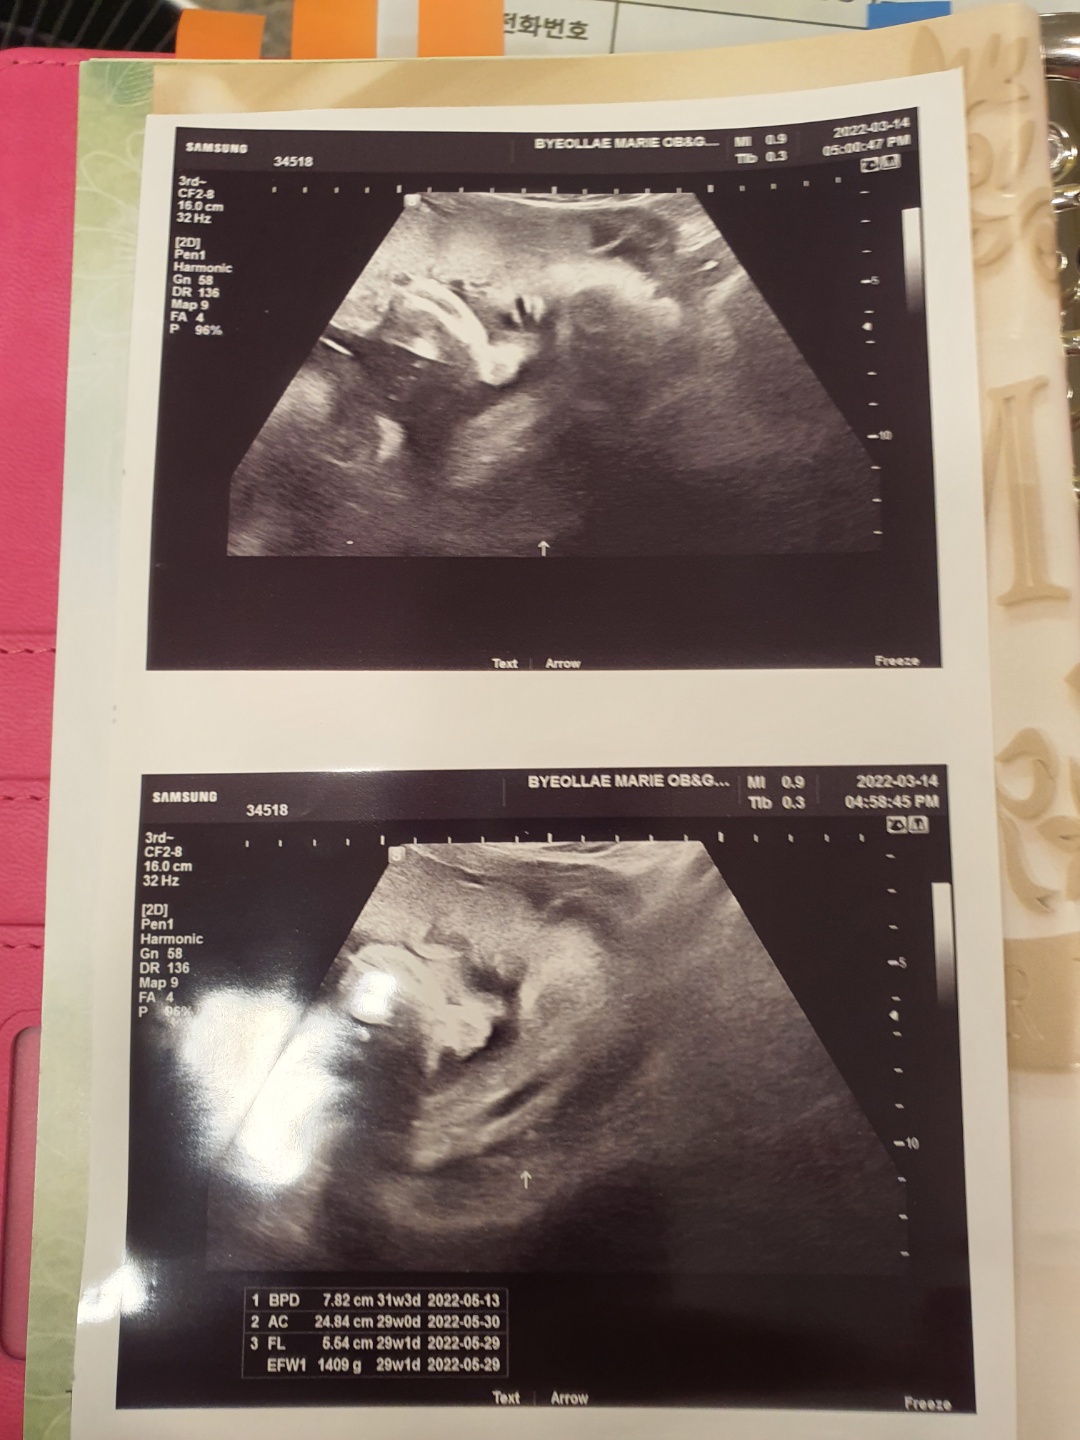

이번 주수에도 역시나 30주 기준 평균 주수에 비해 머리둘레는 살짝 크고, 배 둘레, 다리뼈가 한주 정도 짧게 나왔다. 흑흑 조금 마음이 아프긴 하지만 어쨌든 엄마 뱃속에 있는 상태라 크는 거와 상관없을 거라 생각된다.ㅎㅎ 다행히 체중은 1.4kg 때로 저번보다 살짝 적었던 체중인데 주수 대비 적절하게 나온 편이다.

별로 체크할 사항이 없어서 초음파 사진도 달랑 2장 밖에 안 해주셨다ㅜㅜ.. 앞으로도 이런 식으로 짧고 굵은 초음파 검사를 받을 듯싶다. 체중, 심박수, 머리둘레, 다리 길이 등만 체크하기 위함.

그래도 초음파 검사 중간에 까꿍이가 눈 뜨는 것을 원장님께서 순간포착하여 찍어주셔서 사진으로 남길 수 있었다. 손으로 얼굴 가리고 있어서 속상했는데 잠시나마 엄마, 아빠 기쁘게 해 줘서 고마워🧡💖